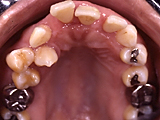

この患者さんの場合は、おそらく「もともとのかみ合わせが歯周病を悪化させ、その歯周病がますます歯並びを悪くする」という悪循環におちいっていたと思います。

治療中は北海道大学附属病院保存科と連携をとって矯正を進めていきました。現在は歯の揺れも生理的な範囲に落ち着き、よく噛めるようになりました。

「前歯が出てきた」ことを気にされて、38歳から治療を開始しました。 不正咬合の種類は「上顎前突」でした。右上の親知らず(智歯)を抜歯し、主にマルチブラケット装置を用いました。前歯の重なりが調整出来るまでは、上顎にバイトプレートという装置も併用しました。治療に際しては、一般的な矯正治療に伴うリスクの説明とともに歯周病が懸念される状態だったため、特に「歯が失われる」「歯槽骨が減少する」可能性ついても説明を行いました。動的治療期間は2年4カ月、保定装置を装着するまでの治療費は¥685,000(税別)でした。